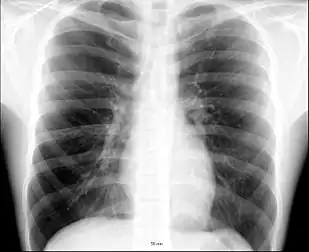

- (anatomy) The portion of the front of the human body from the base of the neck to the top of the abdomen; the thorax. Also the analogous area in other animals.